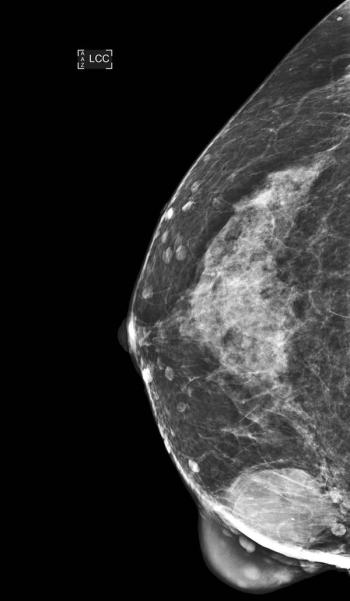

Image IQ: 44-year-old Woman, Screening MammogramByDuke Duncan, MDMay 8th 201544-year-old woman presents for screening mammogram.